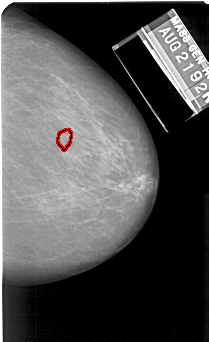

RIGHT_MLO LINES 5491 PIXELS_PER_LINE 3661 BITS_PER_PIXEL 12 RESOLUTION 43.5 OVERLAY

FILE: A_1131_1.RIGHT_MLO.OVERLAY

TOTAL_ABNORMALITIES 1

ABNORMALITY 1

LESION_TYPE CALCIFICATION TYPE PUNCTATE DISTRIBUTION CLUSTERED

ASSESSMENT 4

SUBTLETY 3

PATHOLOGY MALIGNANT

TOTAL_OUTLINES 1

BOUNDARY